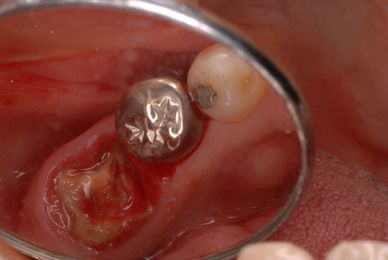

お口の中から差し歯、入れ歯、詰め物を追放しましょう!

口の中の病気を治し、病気を興さない医療を目指します。

二度とお口の中へ変なものを入れなくても済むように

予防に精進いたしましょう!安全な矯正、美容を目指しましょう!